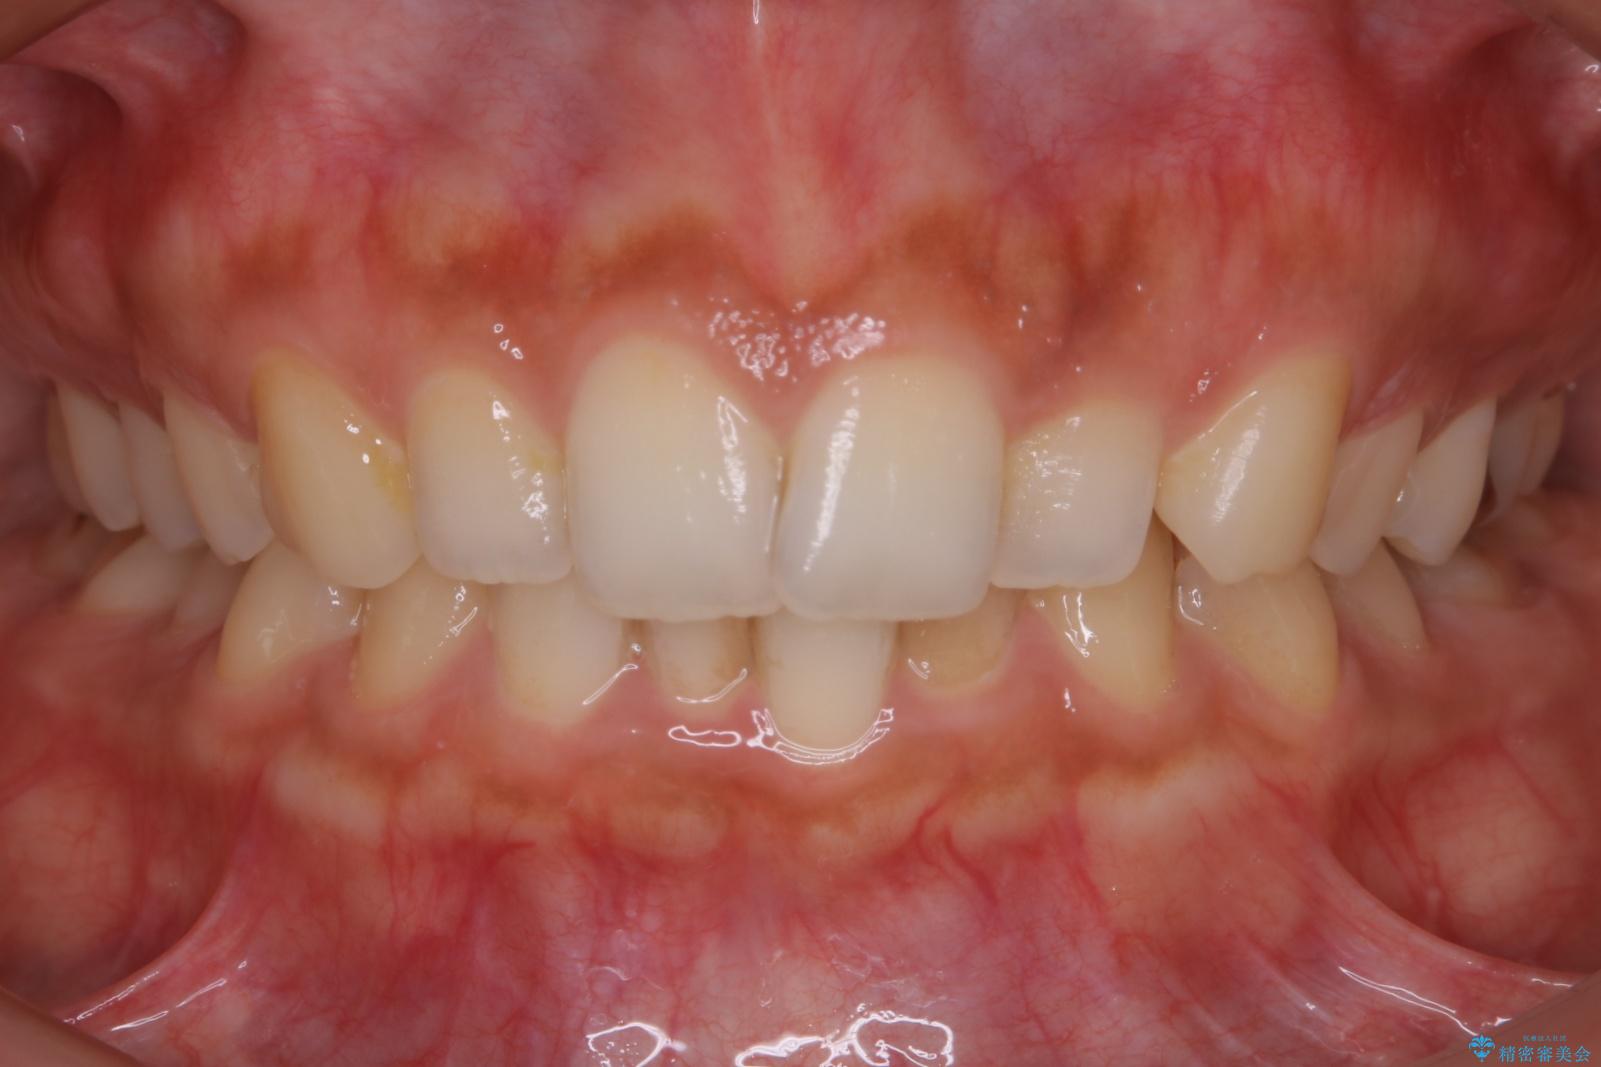

気になるガタツキと噛み合わせを改善したいとご来院されました。

下の歯列よりも上の歯列が前に出ている状態を治すため、マウスピース矯正に加え、患者様にゴムかけのご協力をいただきました。その結果、ガタつきが改善し、上下の噛み合わせが適切な位置で合うようになりました。